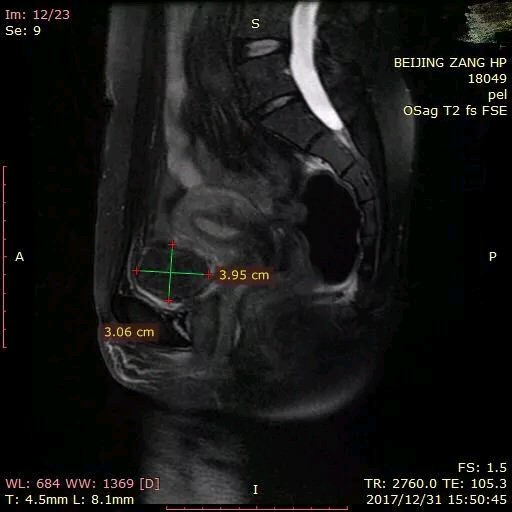

从光盘Dicom的图像上我清晰地看到了她的肌瘤目前只有一个,大概也就是4cm的大小,部位是6型的肌瘤,整个肌瘤基本上都是凸出于子宫外,这样的肌瘤基本上对怀孕不会产生太大的影响的,我就建议她直接尝试带瘤去做移植。浆膜下肌瘤在怀孕以后最大的风险就是在孕早期以后快速增大,有的时候甚至体积可能会增大数十倍,有10~15%的可能会发生红色变性的风险,但是大多数的情况下保守治疗就好。这样的风险是要好过做手术处理肌瘤带来的风险。